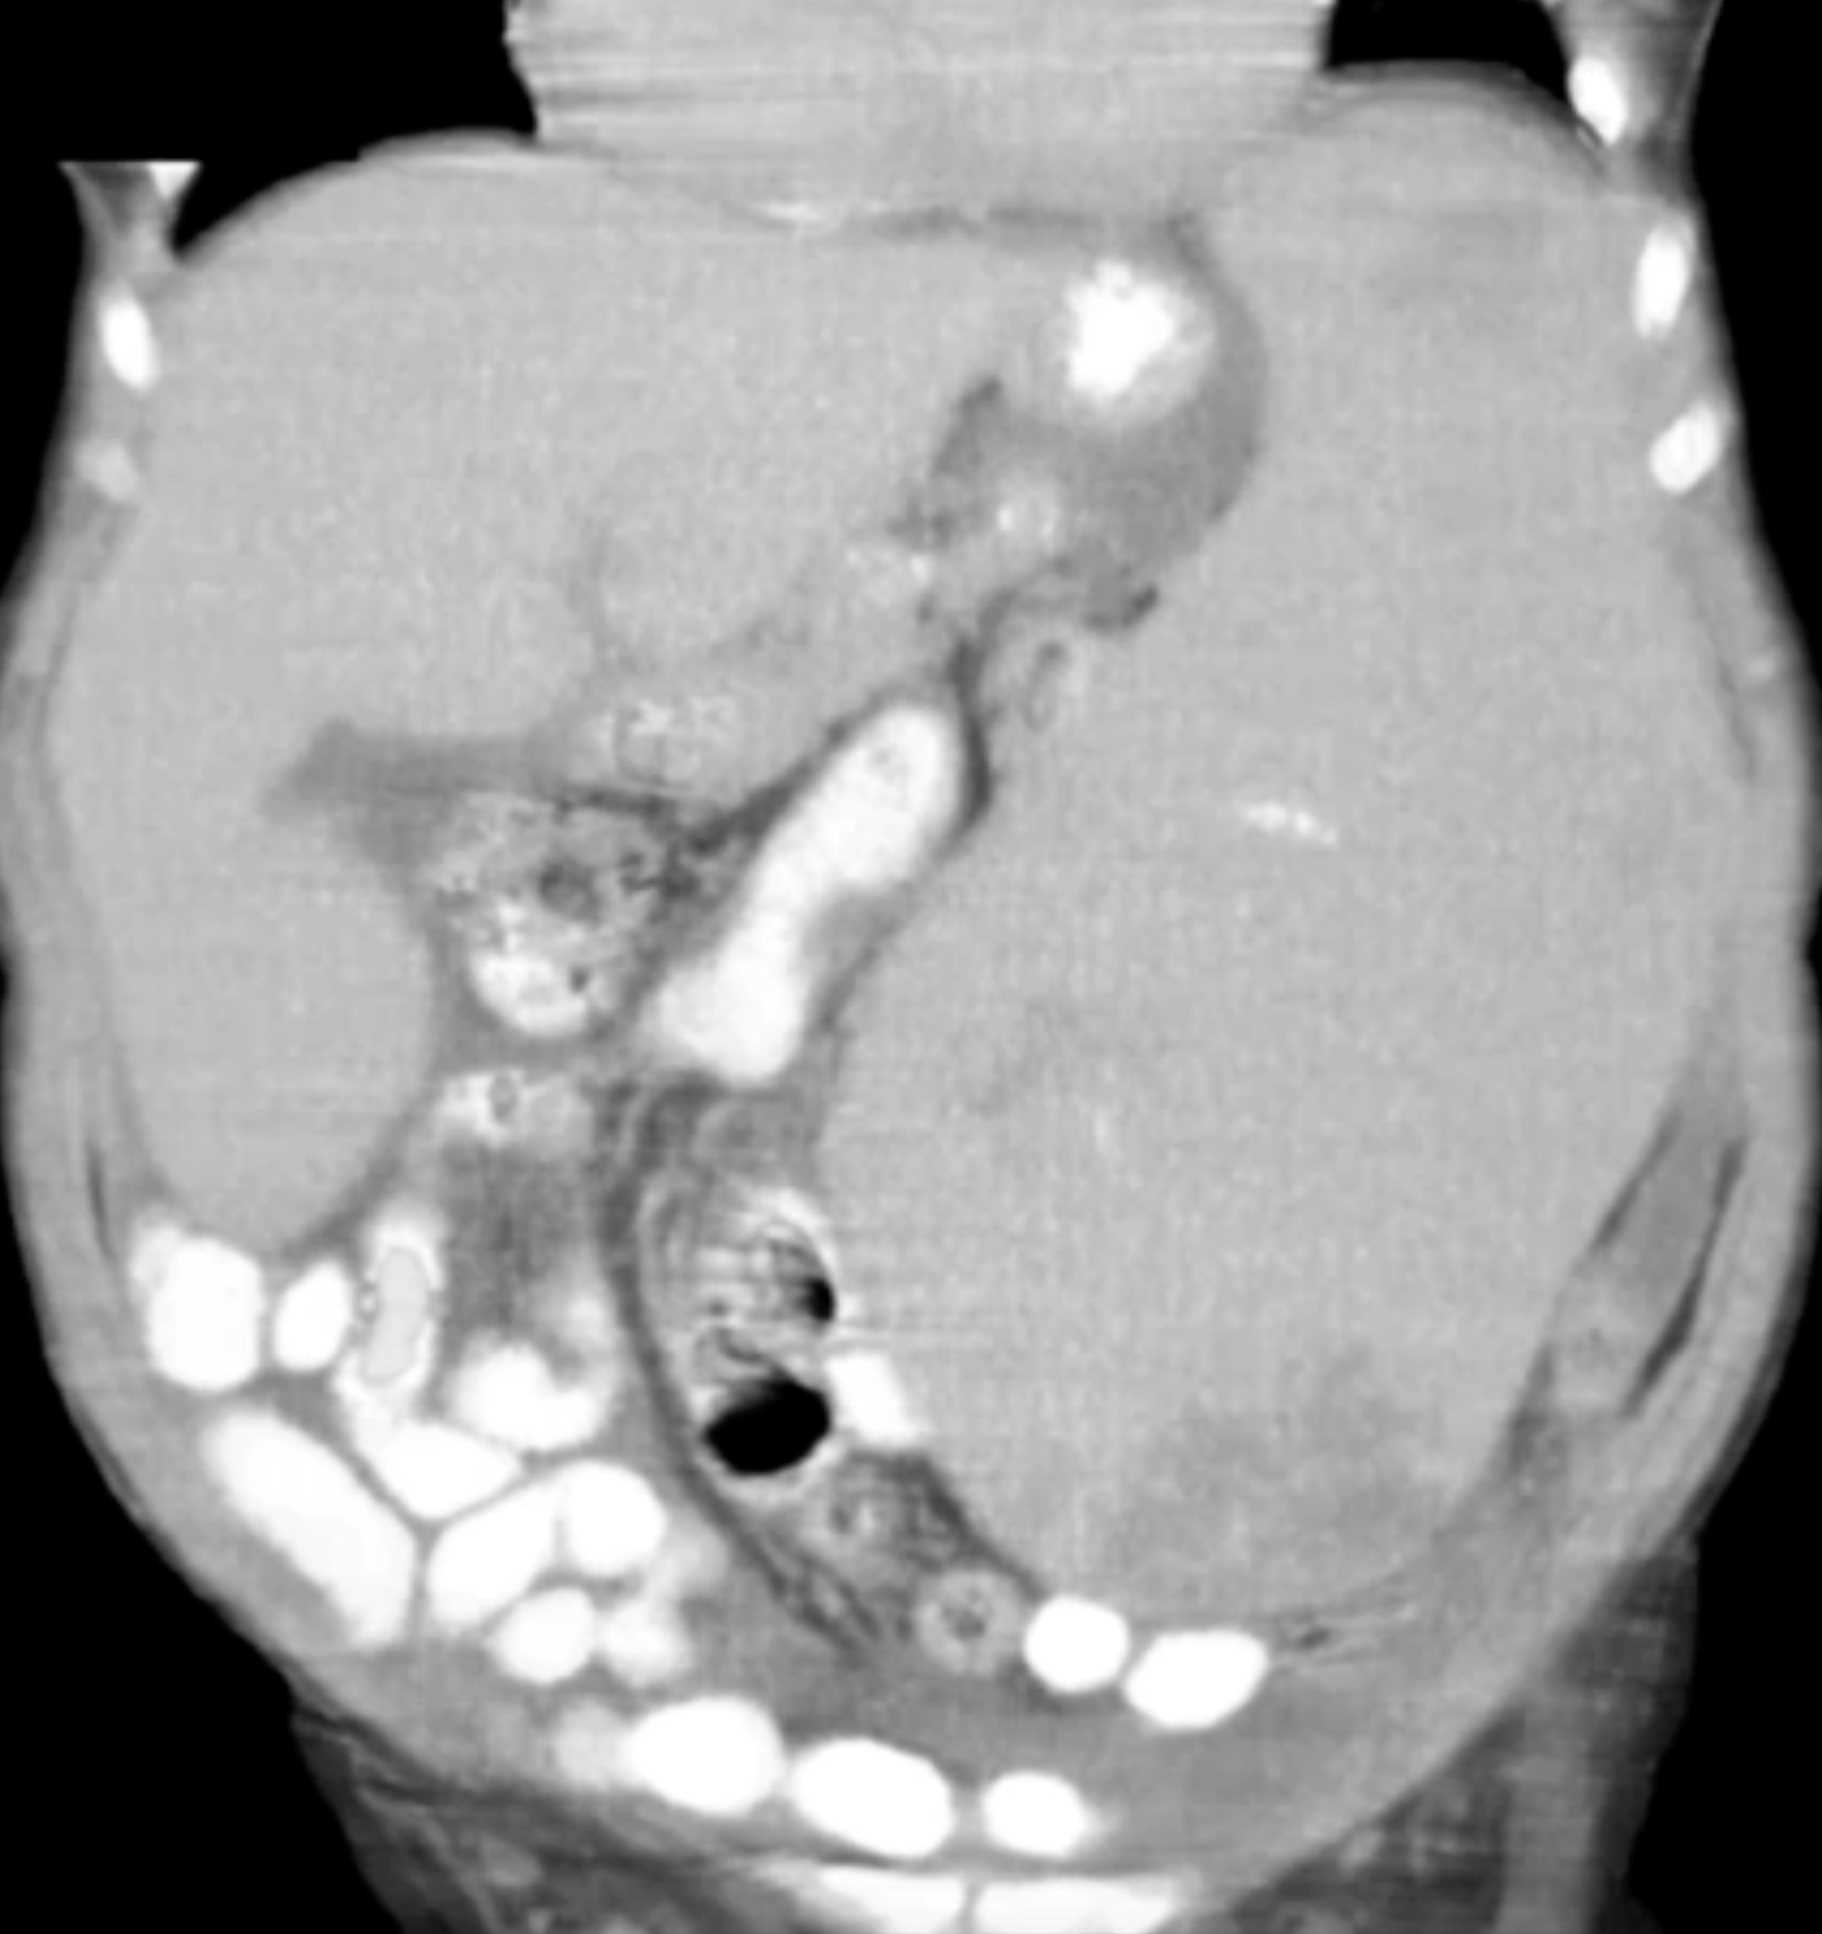

Gaucher's Spleen